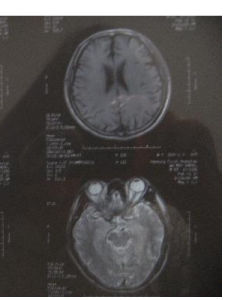

多發性腦梗塞1.影像學檢查

(1)頭顱CTCT掃描是診斷腦梗塞較方便、便宜的檢查。它可明確腦組織壞死(即腦梗塞)的部位、大小、腦水腫的程度等對治療有指導意義,但在發病24小時以內常不能發現病灶。此外,CT的不足在於對腦幹、小腦的病灶顯示不良。

(2)頭顱磁共振掃描該檢查可彌補頭顱CT在24小時內不能發現病灶及對某些部位病灶顯示不良的缺陷,尤其是磁共振血管成像尚能顯示較大的閉塞血管。其不足之處在於價格較貴,而且有些患者由於體內有不能取出的金屬物品,如心臟起博器、金屬牙齒、骨折釘等而不能進行此項檢查,限制了它的使用。